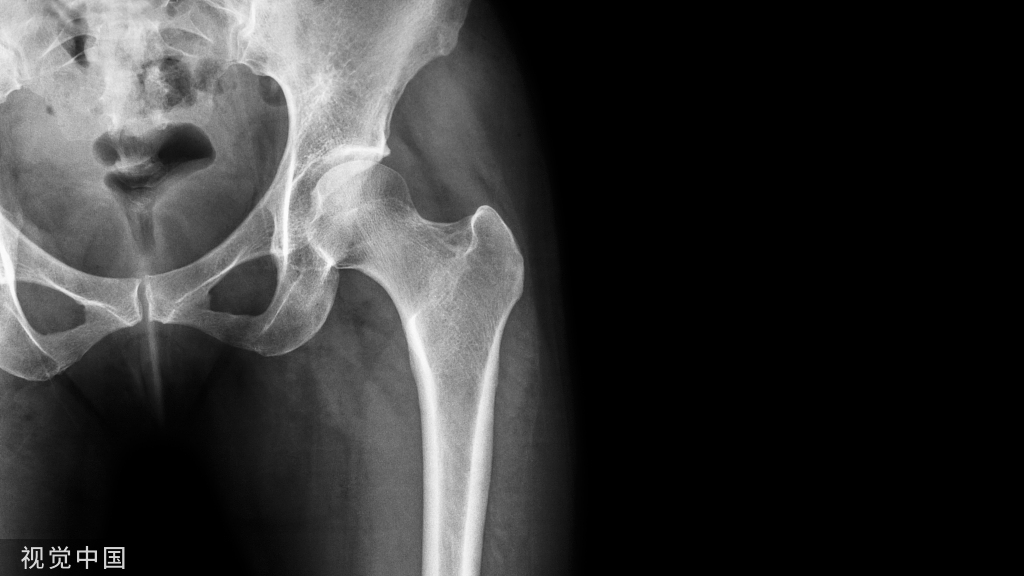

辅助检查:CBCT显示25牙根尖呈喇叭口样敞开,未发育完全,根尖低密度暗影。

CBCT矢状面显示25牙根尖未发育完成,根尖阴影